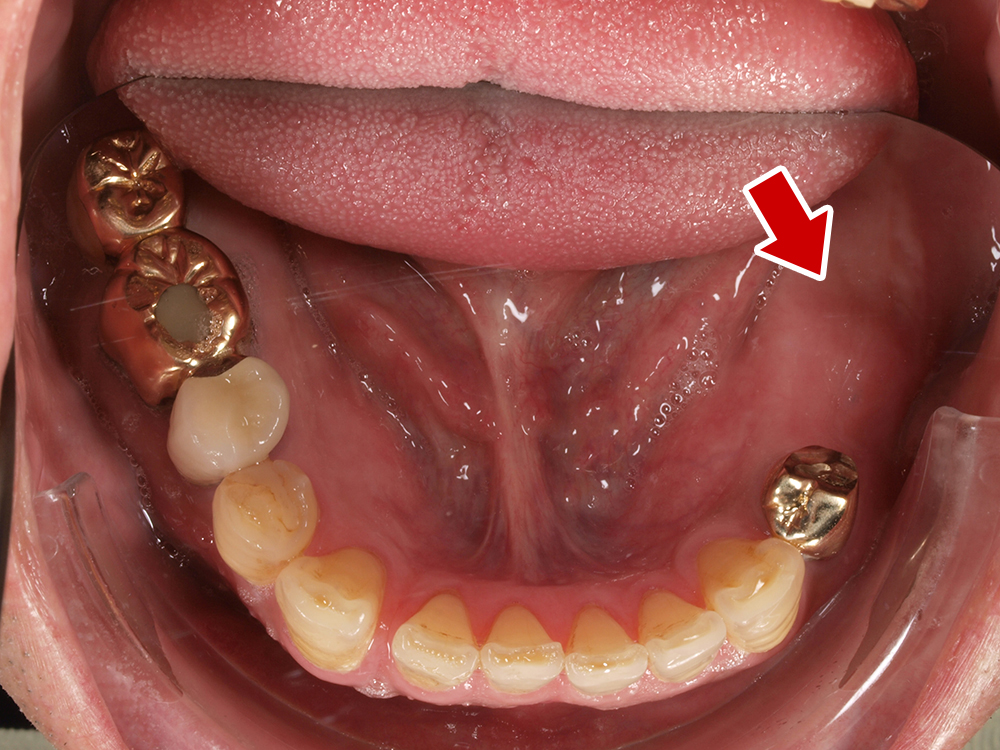

58歳 女性 歯科大学病院 教授からの紹介。

- 主訴

- 左下6番目、右上4番目の歯が長期にわたり痛く、噛めない、

- 処置内容

-

2本インプラント埋入+再生処置。抜歯即時埋入、⇒抜歯を行い、同時にインプラント埋入(即時埋入)

矯正処置

- 治療費用

- 上顎、下顎共に、約40万円(税込)(合計約80万円(税込))

- 治療期間

- 下顎:約6か月、上顎:約9か月

- リスク

- 上部構造物、仮歯の破折、術後の腫れ(3日)、人工歯根脱落リスクがあります

- その他

- 歯科大学病院 教授からの紹介。